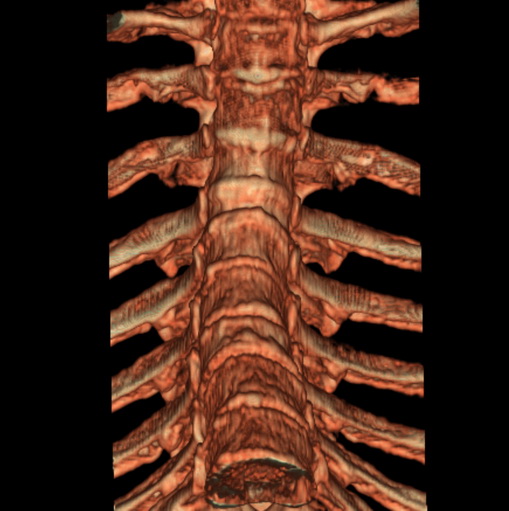

女、73、胸痛、胸闷3个月,无明显外伤病史,x线疑t4、t7陈旧压缩骨折,ct未经明显骨折,请问结论如何报?

老年女性病人,骨质稀疏,有些驼背,t4明显变扁,t7略变扁,椎体边缘无中断,骨小梁排列正常,无嵌插所致致密线。结合无明显外伤史,考虑老年骨质稀疏,慢性压缩改变,正如老年人骨质稀疏椎体呈双凹改变一样。我考虑报:老年骨质稀疏,t4、t7楔形变,脊柱曲度改变(驼背).敬请大家指教。